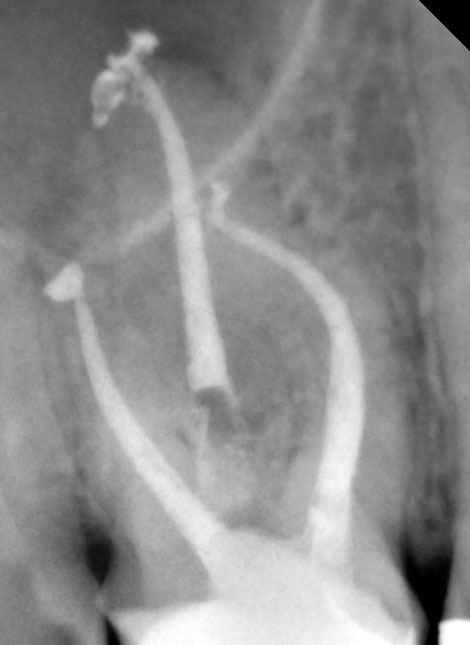

Conhecido popularmente como o tratamento de "matar o nervo" Endodontia é uma especialidade para salvar a extração do dente quando o nervo está infectado, por exemplo, por causa de uma lesão de cárie. O acesso ao nervo do dente (órgão pulpar), o tecido nervoso infectado é removido e selado. O resultado é um  dente desvitalizado, mas saudável e apto para desempenhar suas funções.

tratamento endodontico Dr Alexandre Goulão Dentarmed Almada

Foram discutidos casos de terapia vital e revascularização de dentes necrosados, reabsorções de estruturas radiculares, reparação de perfurações, técnicas de remoção de instrumentos fracturados nos canais, técnicas de identificação e instrumentação de dentes com canais calcificados, atualização em técnicas de desinfeção de canais, técnicas de obturação termoplásticas e técnicas de micro-cirurgia endodontica, temas de grande relevâcia na actualidade da ciência médico-dentária.